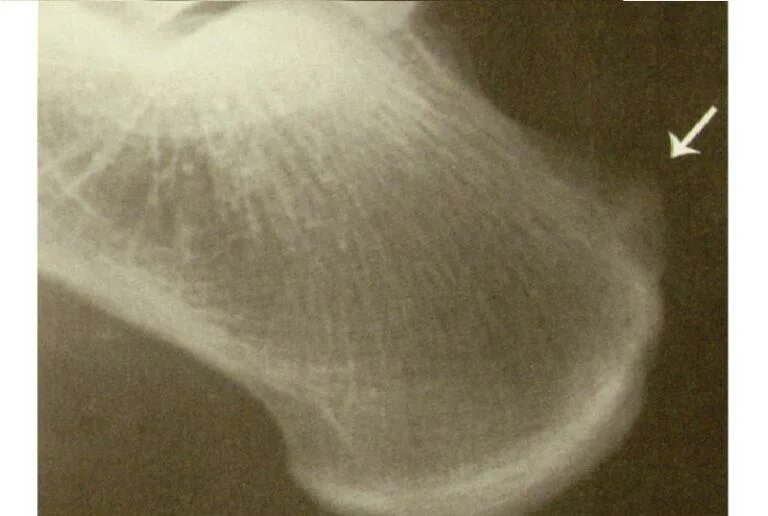

Экзостоз мкб 10